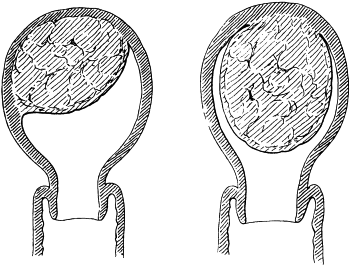

| 310. | Semi-diagrammatic Transverse Section of the Nose | 610 |